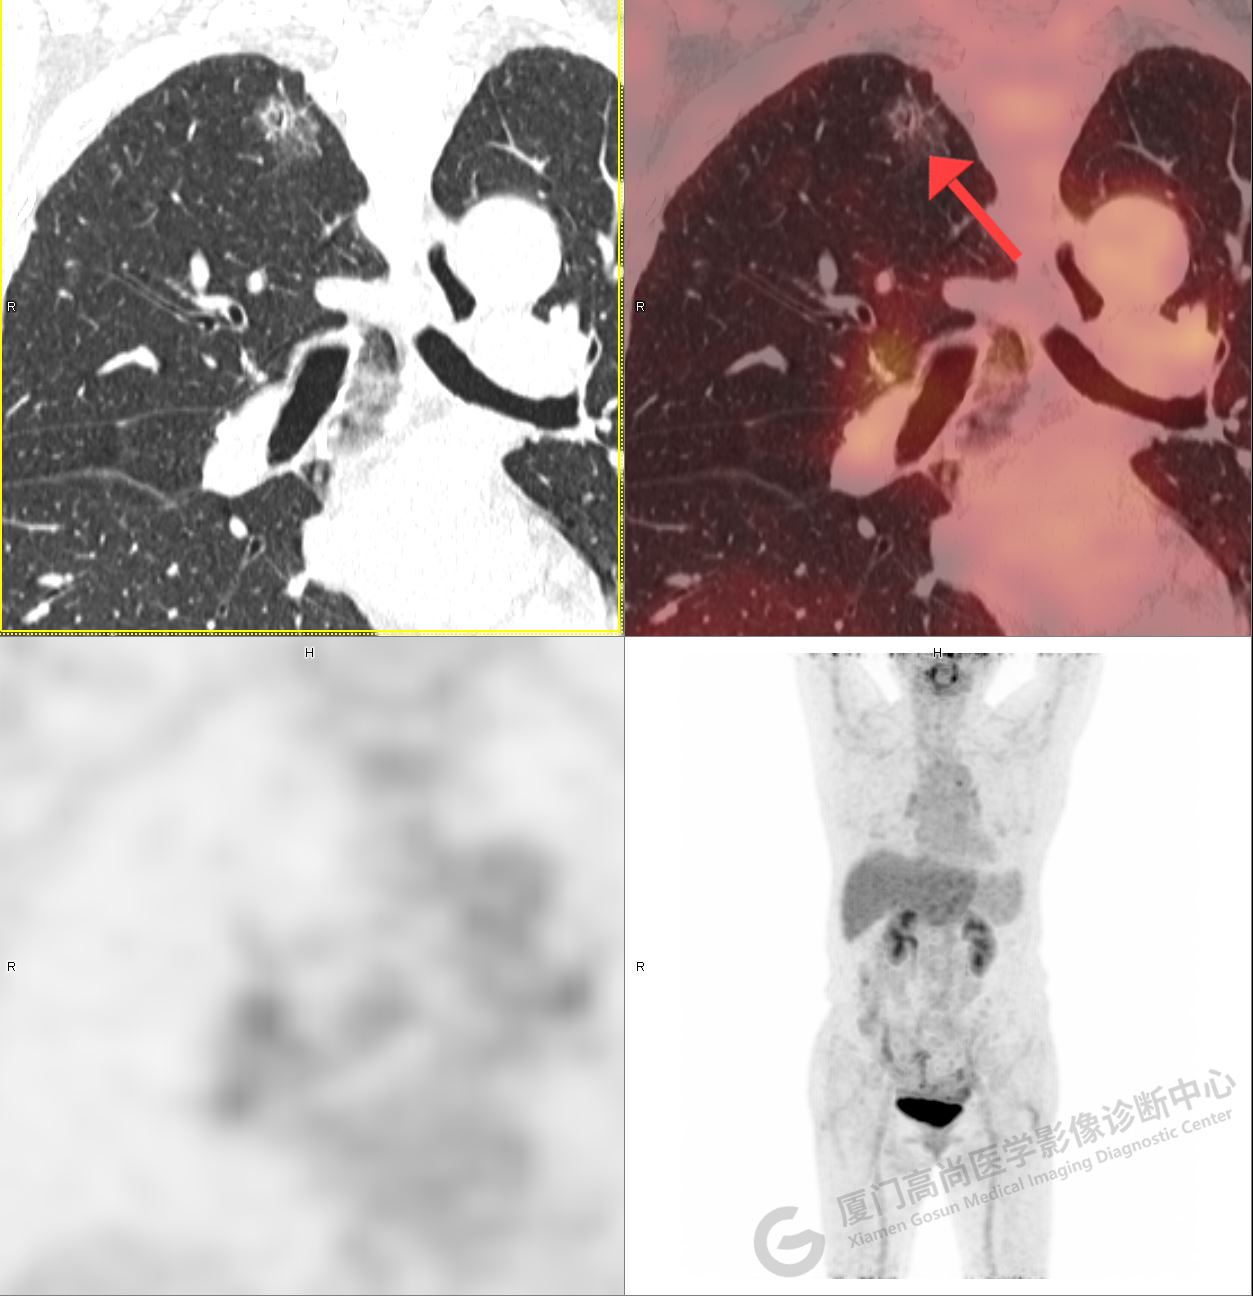

PET/CT影像圖

圖1

圖2

PET/CT示:1、左肺上葉混雜磨玻璃結(jié)節(jié),代謝不高,考慮為浸潤性腺癌,建議病理學(xué)檢查。2、右肺中葉混雜磨玻璃結(jié)節(jié),代謝不高,考慮為腫瘤性病變(微浸潤性腺癌?),建議密切CT復(fù)查。3、右肺上下葉純磨玻璃結(jié)節(jié),代謝不高,雙肺下葉少許結(jié)片影,代謝不高,考慮為炎癥。